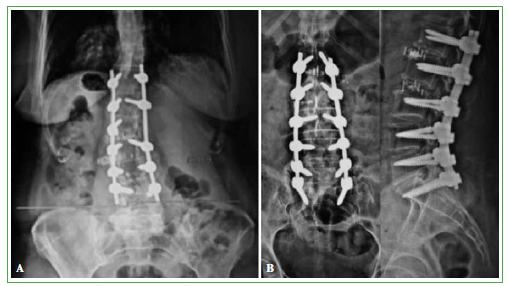

Hubo cuatro casos con subsidencia de la caja intersomática: tres en el platillo inferior, detectada en el primer control, a los 15 días, y uno en el platillo superior, observada en el posoperatorio inmediato (Figura 2). Se detectaron dos casos con migración de la caja (una lateral y otra anterior) en el primer control posoperatorio (Figura 3) y otros dos con mala posición de las cajas, muy laterales, sin secuelas clínicas en los controles sucesivos.

Figura 2.

Paciente con subsidencia del platillo superior. Controles intraoperatorio y posoperatorio inmediato.

Figura 3. A.

Migración lateral. B. Migración anterior.